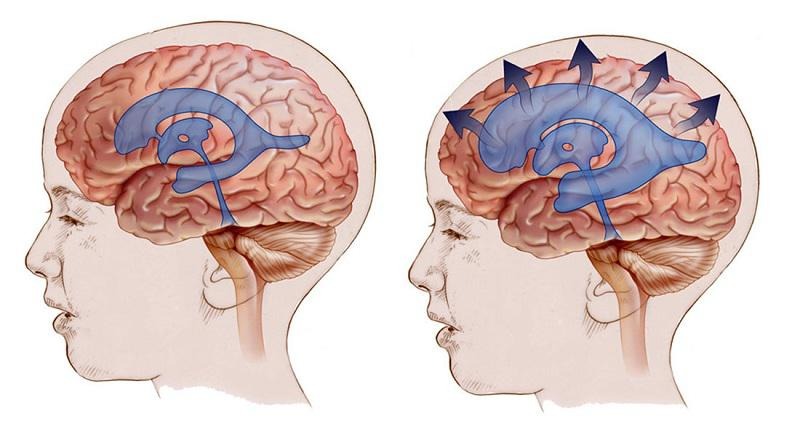

Pseudotumor Cerebri (Idiopathic Intracranial Hypertension)

It is the presence of increased intracranial pressure findings without a brain tumor. CSF content is usually normal, and no underlying cause is identified.